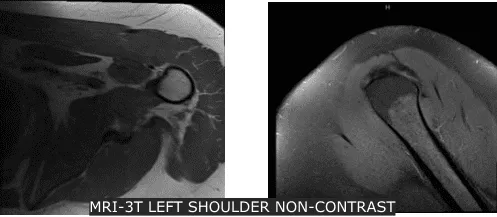

Se revisaron radiografías y se discutió que su hombro izquierdo mostraba radiografías normales. Aconsejamos al paciente que se hiciera una resonancia magnética para ver la causa y descubrimos una rotura de grosor parcial del tendón subescapular, aunque no hay desgarro de alto grado parcial o total del manguito rotador. Presencia de tendinosis supraespinosa e infraespinosa.

Radiografía del hombro izquierdo